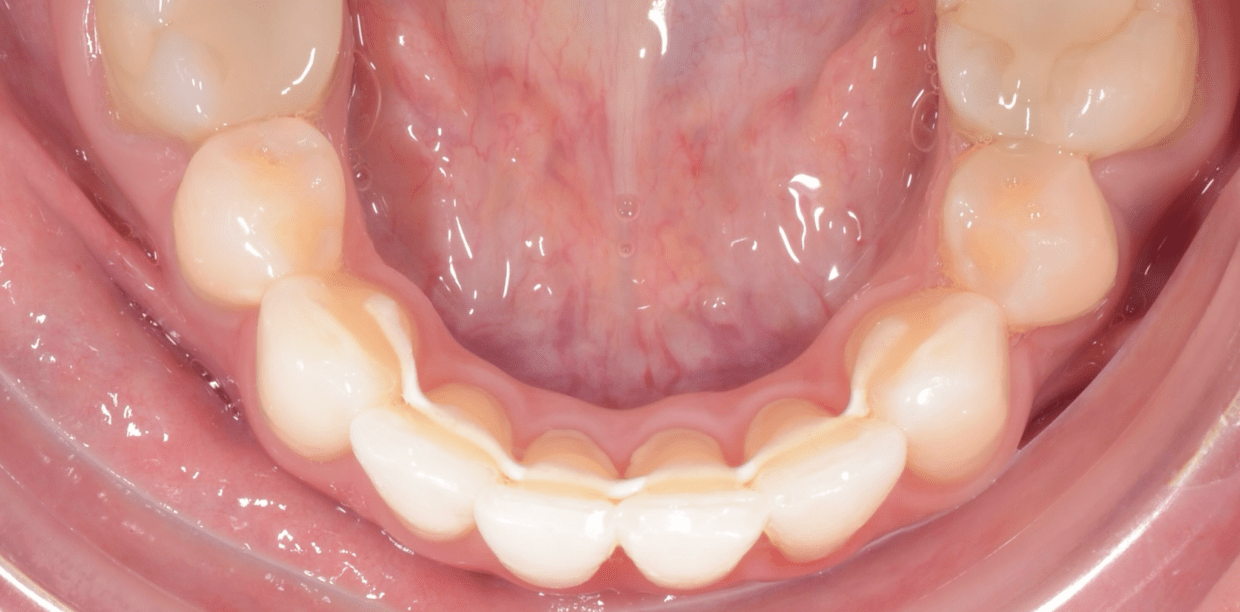

Cas cliniques

Simple - A2

Simple - A2

Simple - A2